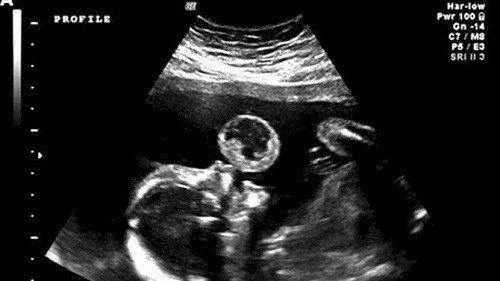

به گزارش زاهدانه، چندی پیش در رسانه‌های خارجی عکسی از سونوگرافی یک جنین منتشر شد و توجه بسیاری را به خود جلب کرد. در این تصویر جنین گویی در بدن مادر در حال آدامس خوردن است.

ماجرا از این قرار است که خانم "گونزالس" از منطقه میامی ایالت فلوریدای آمریکا که در شش ماهگی بارداری خود به سر می برد، زمانی که برای عکسبرداری سونوگرافی به پزشک مراجعه می‌کند، متوجه نکته ای غیرعادی در عکس سونوگرافی می‌شود. در تصویر، جنین انگار دارد یک آدامس بادکنکی باد می کند به طوری که یک شی‌ء گرد جلوی دهان این جنین دختر وجود دارد.

پزشکان با بررسی دقیق تر دریافتند که نوعی تومور مرگبار به نام teratoma جلوی زبان دختر او در حال رشد است، این تومور ها در دروان جنینی شکل می گیرند و از هر 100 هزار تولد بر روی یک جنین اثر می گذارند.